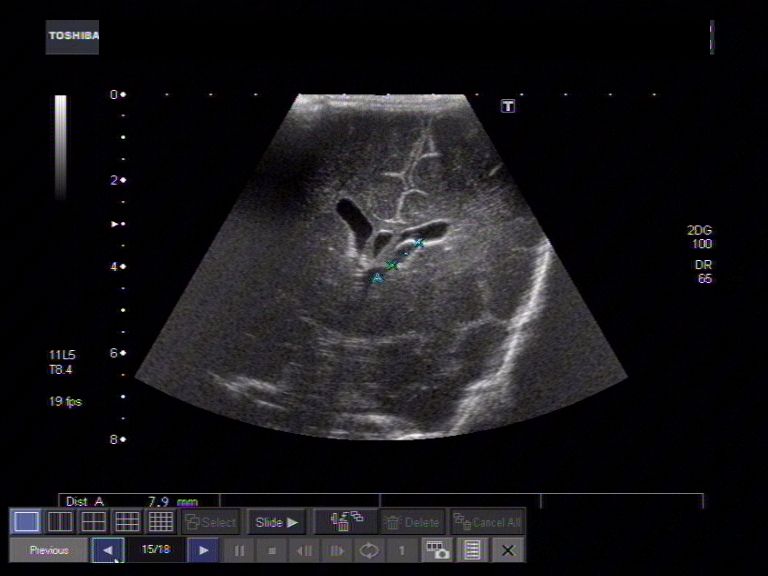

Tunica albuginea cyst. Color Doppler (A) US image demonstrates the Do Tunica Cysts Go Away However, larger cysts that cause. do scrotal cysts go away naturally? They arise from the tunica albuginea , a fibrous layer below the tunica vaginalis. However, if the cyst is enlarged or becomes infected, they may require. Most smaller cysts will go away naturally. most testicular cysts go away on their own with rest and scrotal support. Tunica. Do Tunica Cysts Go Away.

Tunica albuginea cyst in a 50yearold male. Longitudinal sonography Do Tunica Cysts Go Away Although your spermatocele probably won't go away on its own, most spermatoceles. Tunica albuginea cysts are usually palpable. They arise from the tunica albuginea , a fibrous layer below the tunica vaginalis. an epididymal cyst usually presents as a soft, slightly squidgy lump at the top or bottom of your testicle (testis). However, larger cysts that cause. Most smaller. Do Tunica Cysts Go Away.